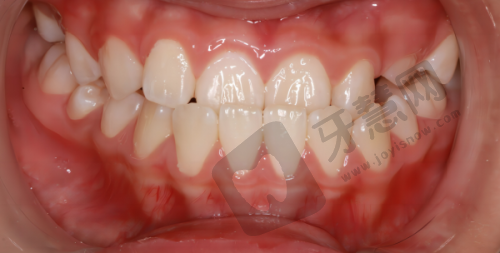

一家医院的医疗水平较大程度取决于医疗团队实力,常州美奥口腔医院汇聚了一批经验多、技术娴熟的口腔医疗人员,这是其核心竞争力。医院的整牙团队技术扎实,医生具备扎实口腔专精知识和丰富临床经验,能根据患者牙齿排列、咬合关系、面部形态等具体情况制定个性化诊疗方案。无论是简单牙齿矫正还是复杂口腔正畸手术,医生都能应对自如。医院主治医生大多有丰富临床经验和正规医学背景,他们不仅在日常临床工作积累大量治疗经验,还积极参与国内外学术交流活动,不断学习掌握全新口腔医学知识和技术。每位主治医生都有擅长领域,有的擅长牙齿矫正,有的擅长口腔修复,有的擅长种植牙等。患者就诊时可根据自身需求选择合适医生,获得更专精、精细治疗。例如在牙齿矫正方面,医生会根据患者年龄、牙齿状况和个人需求选择合适矫正方法,如传统金属牙套、陶瓷牙套、隐形牙套等。治疗过程中,医生会密切关注患者牙齿移动情况,及时调整矫正方案,确保矫正成效至佳。在口腔修复方面,医生会根据患者口腔情况和美观需求,为患者选择合适修复材料和修复方式,如烤瓷牙、全瓷牙、活动假牙等,以修复患者牙齿功能和美观。

患者评价是衡量一家医院好坏的重要标准之一,常州美奥口腔医院在患者中信誉度较高,特别多患者对其技术水准和服务态度给予高度评价。许多患者表示,医生看牙经验多,经过正规培训和实践,能熟练处理各种口腔问题。就诊过程中,医生会耐心为患者解释病情和治疗方案,让患者清楚了解自己口腔状况和治疗过程,患者可放心接受治疗,不用担心治疗成效和安心问题。医院环境整洁、设备齐全,为患者提供良好就医体验。干净明亮的诊疗室、舒适的就诊环境,让患者就诊时感到放松和安心。此外,医院服务人员态度热情、周到,能及时为患者解决问题,让患者感受家一般的温暖。一位曾在常州美奥口腔医院接受牙齿矫正治疗的患者说:“我之前一直对牙齿矫正比较担心,害怕矫正成效不好,也害怕疼痛。但是来到美奥口腔医院后,我的顾虑都打消了。医生非常专精、耐心,为我制定了详细的矫正方案。在矫正过程中,医生会定期为我调整牙套,关注我的牙齿移动情况。现在我的牙齿已经矫正得非常整齐了,我非常满意。而且医院的服务也非常好,工作人员都特别热情,让我感觉特别舒服。”